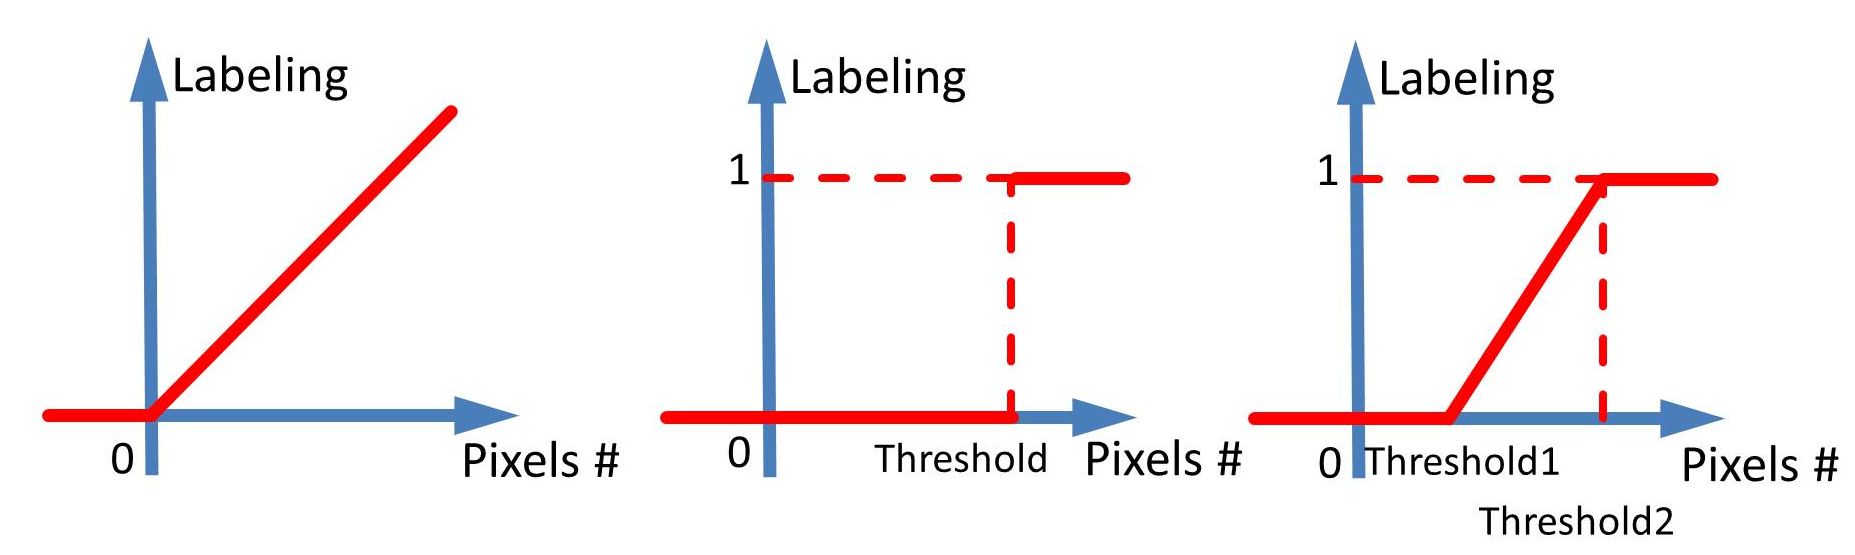

Binary or Continuously Valued Regression: There are several options to form the regression labels for each image. One straightforward scheme is to count the total number of pixels annotated per ILD disease, which represents its severity (Fig. 3 Left). The step function to represent the presence (1) or absence (0) of the disease (Fig. 3 Middle) is also possible. The binarizing threshold may be defined using clinical knowledge: if the pixel number is , the label is set to be 1; otherwise as 0. A more sophisticated label transfer model is a piecewise linear function of the pixel counts with , mapping pixel counts to the a range of (Fig. 3 Right). Diseases with the number of total pixels but are linearly interpolated to between and .

4.4 Results on Multi-label Regression CNN

We can treat the continuously-valued output vector, either in the form of pixel number counts or binary presence status, as the “classification confidence scores” after the multi-label regression CNN processes an input CT image. These regressed confidence scores can be compared against the ground truth binary ILD labels obtained by thresholding on as in Sec. 4.3. In this manner, ILD classification receiver operating characteristic (ROC) curves are generated. Our experiments are conducted via the three label converting functions or plots in Fig. 3. Two variations of CNN regression outputs to match the ILD occupied pixel numbers per-slice, or the binary ILD presence labels produce similar quantitative ILD classification results. The piecewise linear transformation (Fig. 3 Right) yields slightly inferior results.